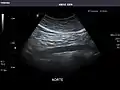

Aorta: Visualized portions normal in caliber, 16 x 15 mm.

Aorta